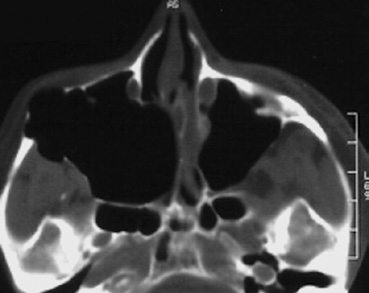

Bei anhaltender klinischer Symptomatik nach erfolgter Zahnbehandlung sollten gegebenenfalls eine rhinochirurgische Behandlung zur Verbesserung der maxillären Clearance und Entfernung des entzündlichen Débris aus der Höhle über einen erweiterten supraturbinalen Zugang eingeleitet werden. Kritisch sind überstopfte Füllmaterialien, da diese gehäuft zur Ausbildung von Pilzkugeln in der KH führen. Histologisch werden dabei überwiegend Pilzhyphen und typische Fruchtköpfe gefunden. Mikrobiologisch lassen sich meist Aspergillus-Stämme nachweisen. Charakteristisch ist die Kalzifizierung der Pilzhyphen, die bei einer Verdichtung kalkdichte Konkremente bilden und als Rhinolithen im CT oder DVT erkennbar werden (Abb. 10) [14]. Einer chirurgischen Sanierung durch vollständige Entfernung des Pilzmaterials über einen erweiterten endonasalen Zugangsweg ist hier der Vorrang einzuräumen [15]. Die Erfolgsrate nach diesen Behandlungen kann als sehr hoch eingeschätzt werden (Abb. 11a und b).

Eine Übersicht neoplastischer Formationen in der Kieferhöhle und auch in der unmittelbaren Umgebung ist in der Tabelle 3 zu sehen. In Bezug auf das Auftreten aller malignen Neubildungen sind sie vergleichsweise selten. Dennoch sind die malignen Erkrankungen der Kieferhöhle viel häufiger als die der anderen NNH [7,21–23). Im klinischen Alltag hat sich gezeigt, dass eine Früherkennung schwierig ist, da sich die Symptome nur wenig von der entzündlichen Symptomatik unterscheiden. Suspekt sind immer Formveränderungen der Kieferhöhlenwandungen und Okklusionsstörungen. Aber auch persistierende Schmerzen (Abb. 15a bis c) sollten als Warnsignal bewertet werden.